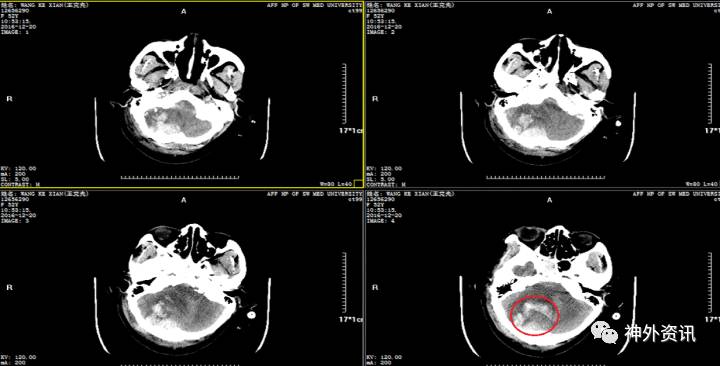

辅助检查:入院头颅CT示:①左侧额颞顶部硬膜下血肿;右侧枕部硬膜外血肿;左侧额颞叶及右侧小脑半球多发挫裂伤伴血肿形成;蛛网膜下腔积血;大脑镰下疝。②枕骨右侧骨折;蝶窦后壁骨折,累及枕骨斜坡;蝶窦右侧积液/积血,鞍区少许积气;枕部头皮肿胀。

初步诊断:重型内开放性颅脑损伤:①左额颞及右小脑半球脑挫裂伤伴血肿,②左额颞顶枕部急性硬膜下血肿,③左额部硬膜外血肿,④颅底骨折,⑤右枕骨骨折,⑥左颞部头皮血肿

空心箭头:小脑血肿,约2cm*2cm*2cm;实心箭头:左额叶脑挫裂伤伴硬膜外血肿